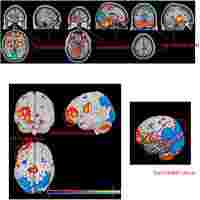

| Description | Journal: Neuropsychiatric disease and treatment Validation of abnormal glucose metabolism associated with Parkinsons disease in Chinese participants based on 18F-fluorodeoxyglucose positron emission tomography imaging Rongbing Jin,1,* Jingjie Ge,2,* Ping Wu,2 Jiaying Lu,2 Huiwei Zhang,2 Jian Wang,3 Jianjun Wu,3 Xianhua Han,2 Weishan Zhang,2 Chuantao Zuo2,4 1Department of Nuclear Medicine, Daping Hospital, Army Medical University, Chongqing 400042, China; 2PET Center, Huashan Hospital, Fudan University, Shanghai 200235, China; 3Department of Neurology, Huashan Hospital, Fudan University, Shanghai 200040, China; 4Institute of Functional and Molecular Medical Imaging, Fudan University, Shanghai 200433, China *These authors contributed equally to this work Purpose: We previously identified disease-related cerebral metabolic characteristics associated with Parkinson's disease (PD) in the Chinese population using 18F-fluorodeoxyglucose (FDG) positron emission tomography (PET)/computed tomography (CT) imaging. The present study aims to assess data reproducibility and robustness of the metabolic activity characteristics across independent cohorts. Patients and methods: Forty-eight patients with PD and 48 healthy controls from Chongqing district, in addition to 33 patients with PD and 33 healthy controls from Shanghai district were recruited. Each subject underwent brain 18F-FDG PET/CT imaging in a resting state. Based on the brain images, differences between the groups and PD-related cerebral metabolic activities were graphically and quantitatively evaluated. Results: Both PD patient cohorts exhibited analogous cerebral patterns characterized by metabolic increase in the putamen, globus pallidus, thalamus, pons, sensorimotor cortex and cerebellum, along with metabolic decrease in parieto-occipital areas. Additionally, the metabolic pattern was highly indicative of the disease, with a significant elevation in PD patients compared with healthy controls (p |